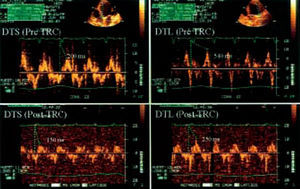

- Retraso septo-pared lateral (RSL). La diferencia (ms) valorada por eco-Doppler tisular entre el inicio del complejo QRS y la velocidad sistólica máxima de cada región ventricular en el eje apical de 4 cámaras.

De la misma manera, la resincronización también se asoció a una disminución estadísticamente significativa (p = 0,007) del RSL basal (111,4 ± 30,9 ms) en relación con el RSL a los 3 meses con el dispositivo conectado (61,9 ± 21,3 ms; fig. 3). El RSL basal fue similar al RSL con el dispositivo desconectado al final del seguimiento (111,4 ± 30,9 frente a 115,3 ± 28,6; p = 0,58).

Fig. 3. Cuantificación del retraso septo-pared lateral mediante Doppler tisular. El panel superior muestra los valores medidos antes de la resincronización, obteniéndose un retraso septo-pared lateral de 340 ms. El panel inferior muestra los valores obtenidos tras la resincronización, con un retraso septo-pared lateral que mejora hasta 100 ms.